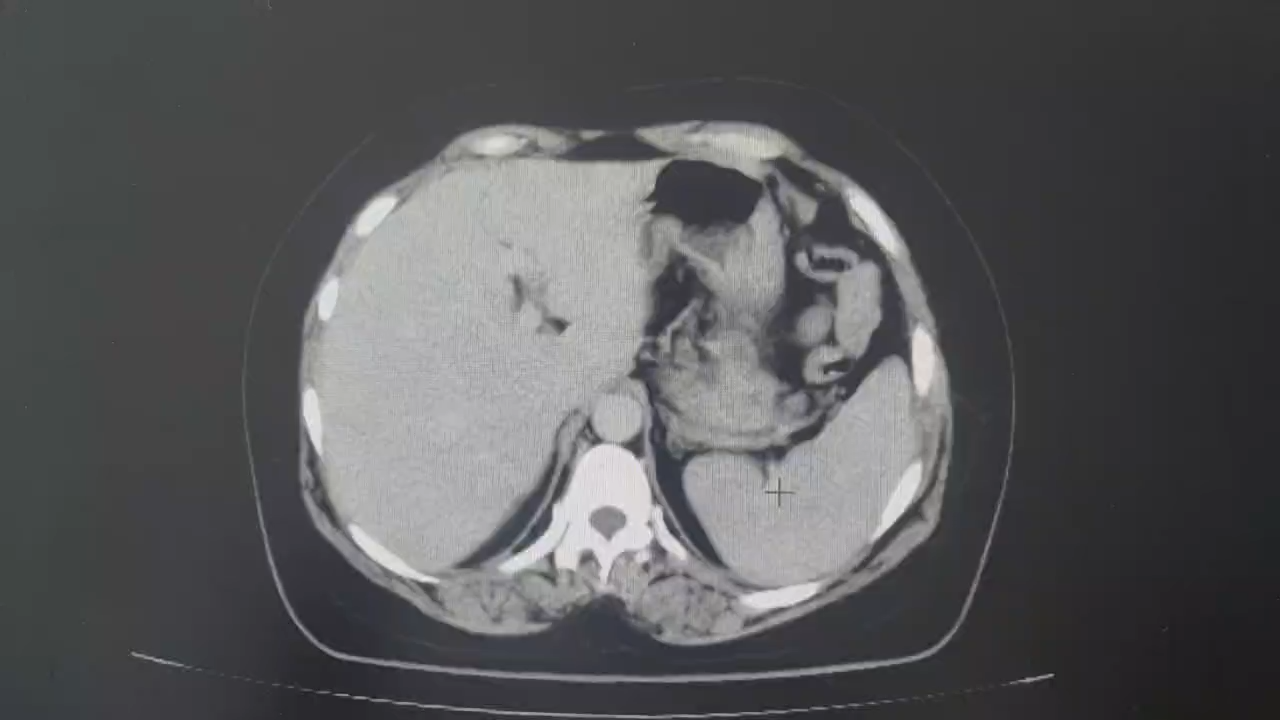

腹部增强CT检查:

门脉期:

术前讨论:科室集体讨论后认为患者腹腔内肿物来源于卵巢的可能性较大,但也不排除其他来源,尤其是肠系膜来源,从腹部增强CT来看,患者腹腔内肿物供血动脉来源于肠系膜上动脉根部,即空肠第二支,空肠第一分支动脉位于肿瘤上极左侧,受压偏移明显,肠系膜上动脉及上静脉主干均明显受压变形。从CT上来看,肿瘤内没有明显强化表现,像囊性肿瘤。部分医生认为可以选择腔镜手术,先进行减压后再切除,但是考虑到这么大的肿瘤,万一是恶性的,先穿刺减压就违反了无瘤原则。最后决定备血后进行开放手术治疗。